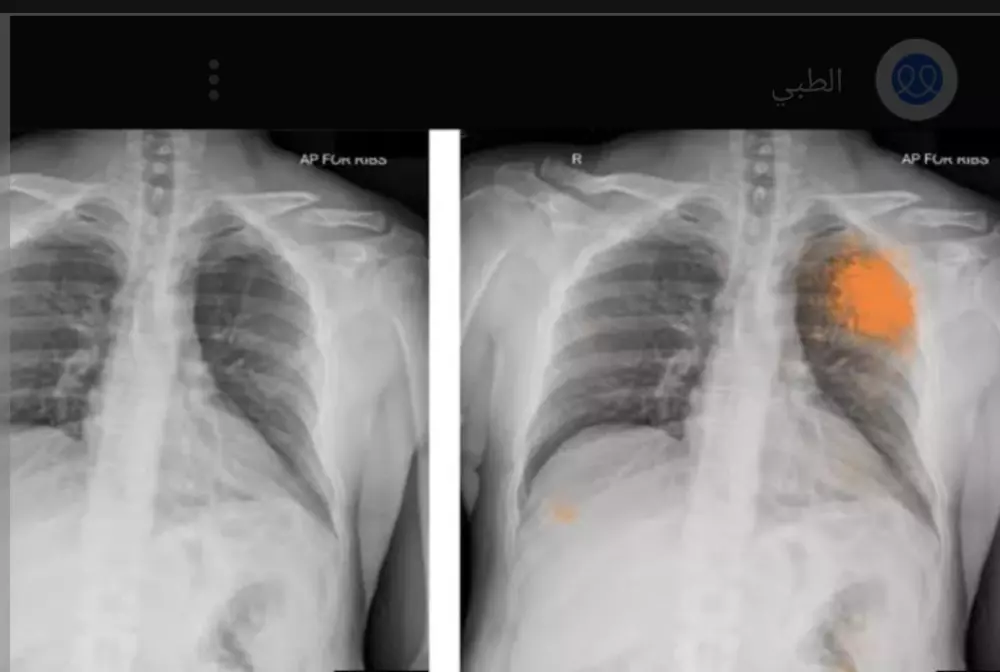

قراءة تقارير التحاليل والأشعه وتقديم ملخص ووصف استشاري عام دون تشخيص أو وصفه علاجيه وتوجيهك لزيارة الطبيب المختص ثمن قراءة تقرير التحليل 10 دولار لكل تقريرين والأشعه كذلك وإن كان هناك استشارات أو أسئله فسيكون ثمن ال5 أسئله 10 دولار ونؤكد على أن المعلومات المقدمه لا تغني عن زيارة الطبيب ولا تعتبر تشخيص نهائي ولا أصف لك دواء فقط اطمئنك على حالتك عوفيتم